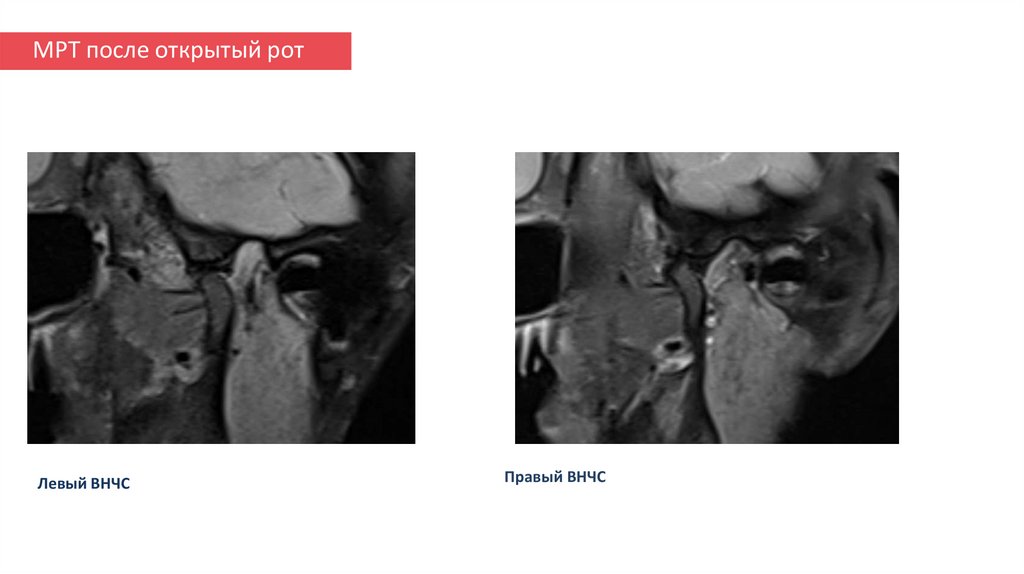

ПРОБЛЕМНЫЙ ЛИСТ

19. МРТ после закрытый рот

Левый ВНЧС

Правый ВНЧС

20. МРТ после открытый рот